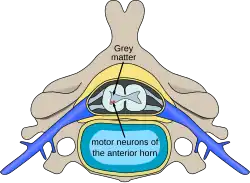

- Alpha motor neurons innervate extrafusal muscle fibers, which are the main force-generating component of a muscle. Their cell bodies are in the ventral horn of the spinal cord and they are sometimes called ventral horn cells. A single motor neuron may synapse with 150 muscle fibers on average.[20] The motor neuron and all of the muscle fibers to which it connects is a motor unit. Motor units are split up into 3 categories:[21]